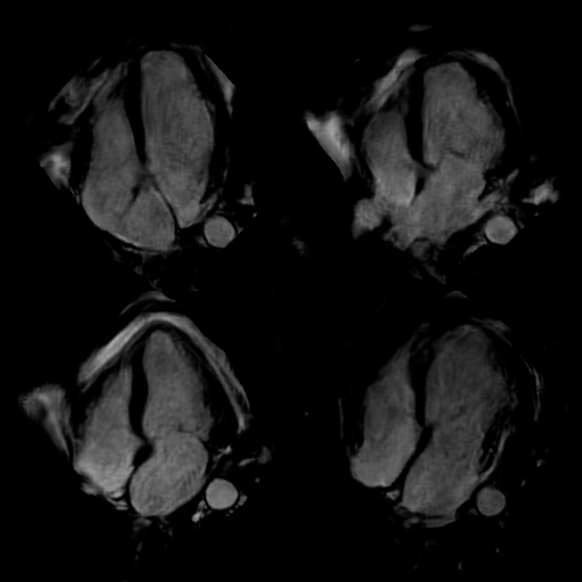

Refer to captionABC

Figure 8: Echocardiography (column A), generated cardiac MRI (column B), and original cardiac MRI (column C) frames across different points of the cardiac cycle for 10thsuperscript10𝑡10^{th}10 start_POSTSUPERSCRIPT italic_t italic_h end_POSTSUPERSCRIPT patient.

To assess the visual quality of the generated cardiac MRI views, we conducted a qualitative evaluation based on several key criteria. Using the test set, we performed echocardiography frame transformation, and compared it with its original echocardiography and time-registered cardiac MRI views as shown in Fig. 8.

Secondly, we check whether the generated views represent the actual cardiac motion throughout the cardiac cycle. This includes ensuring the smooth and consistent transition between systole and diastolic phases and the corresponding movement of the muscles. The consistent transformation of muscle movement’s pace indicates the models can incorporate dynamic information through temporal space. This is especially crucial for RWMA detection to diagnose any onset of myocardial ischemia and infarction (MI).

Finally, we consider the overall visual consistency and quality of the generated cardiac MRI views. This involved checking for artifacts, smoothness, and consistency of the visible arteries and other cardiac features. This is particularly important to validate that the model is not hallucinating while generating the view, but incorporating the information from the source view.

Some typical transformation results over the test set are shown in Fig. 8 along with the source and target views. An extensive set of additional results from the test set are provided in Appendix A111The rest of the results are available in Appendix A. and also in video format online222https://github.com/ilkeadalioglu/Echo2MRI.

Results indicate that the quality of the transformed cardiac MRI views can mostly satisfy the aforementioned criteria and usually present a similar or sometimes even better visual quality than the corresponding actual (target) cardiac MRI views. To validate this claim, we further performed a “Confusion Test” as part of the domain expert evaluation, which will be presented next.